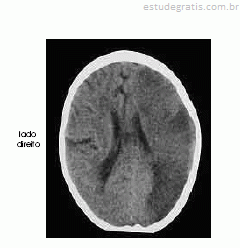

Um homem com 67 anos de idade, lavrador, deu entrada no pronto-socorro após ter sido encontrado, em sua casa, no chão e com dificuldade para falar e deambular. O paciente morava sozinho e os parentes não sabiam informar sobre uso de medicações ou patologias pregressas. Na avaliação, o neurologista identificou afasia mista, hemianopsia homônima direita e hemiparesia direita de predomínio braquifacial. Apesar de apresentar sonolência, o paciente ficava alerta ao chamado. A pressão arterial era de 180 mmHg × 90 mmHg. Foram solicitados exames complementares e de imagem, dos quais uma das imagens é reproduzida abaixo.